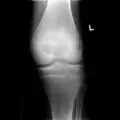

A variety of imaging studies can be used to diagnose chondroblastoma, with radiographs being the most common.[10][8] Laboratory studies are not considered useful.[14] Classical chondroblastoma (appearing on long bones) appears as a well-defined eccentric oval or round lytic lesion that usually involves the adjacent bone cortex without periosteal reaction.[10][13] A sclerotic margin can be seen in some cases.[10][13] For long bone chondroblastomas the tumor is typically contained to the epiphysis or apophysis but may extend through the epiphyseal plate.[10][13] Chondroblastomas are usually located in the medullary portion of bones and can, in some cases, include the metaphysis.[10][13] However, true metaphyseal chondroblastomas are rare and are typically the result of an extension from a neighboring epiphyseal legion.[10][13] Most lesions are less than 4 cm.[10] A mottled appearance on the radiograph is not atypical and indicates areas of calcification which is commonly associated with skeletally immature patients.[10] Additionally, one-third of all cases involve aneurysmal bone cysts which are thought to be the result of stress, trauma or hemorrhage.[10] In cases involving older patients or flat bones, typical radiographic presentation is not as common and may mimic aggressive processes.[10][13]

3. X-ray of chondroblastoma of large long bone of lower leg, near the knee